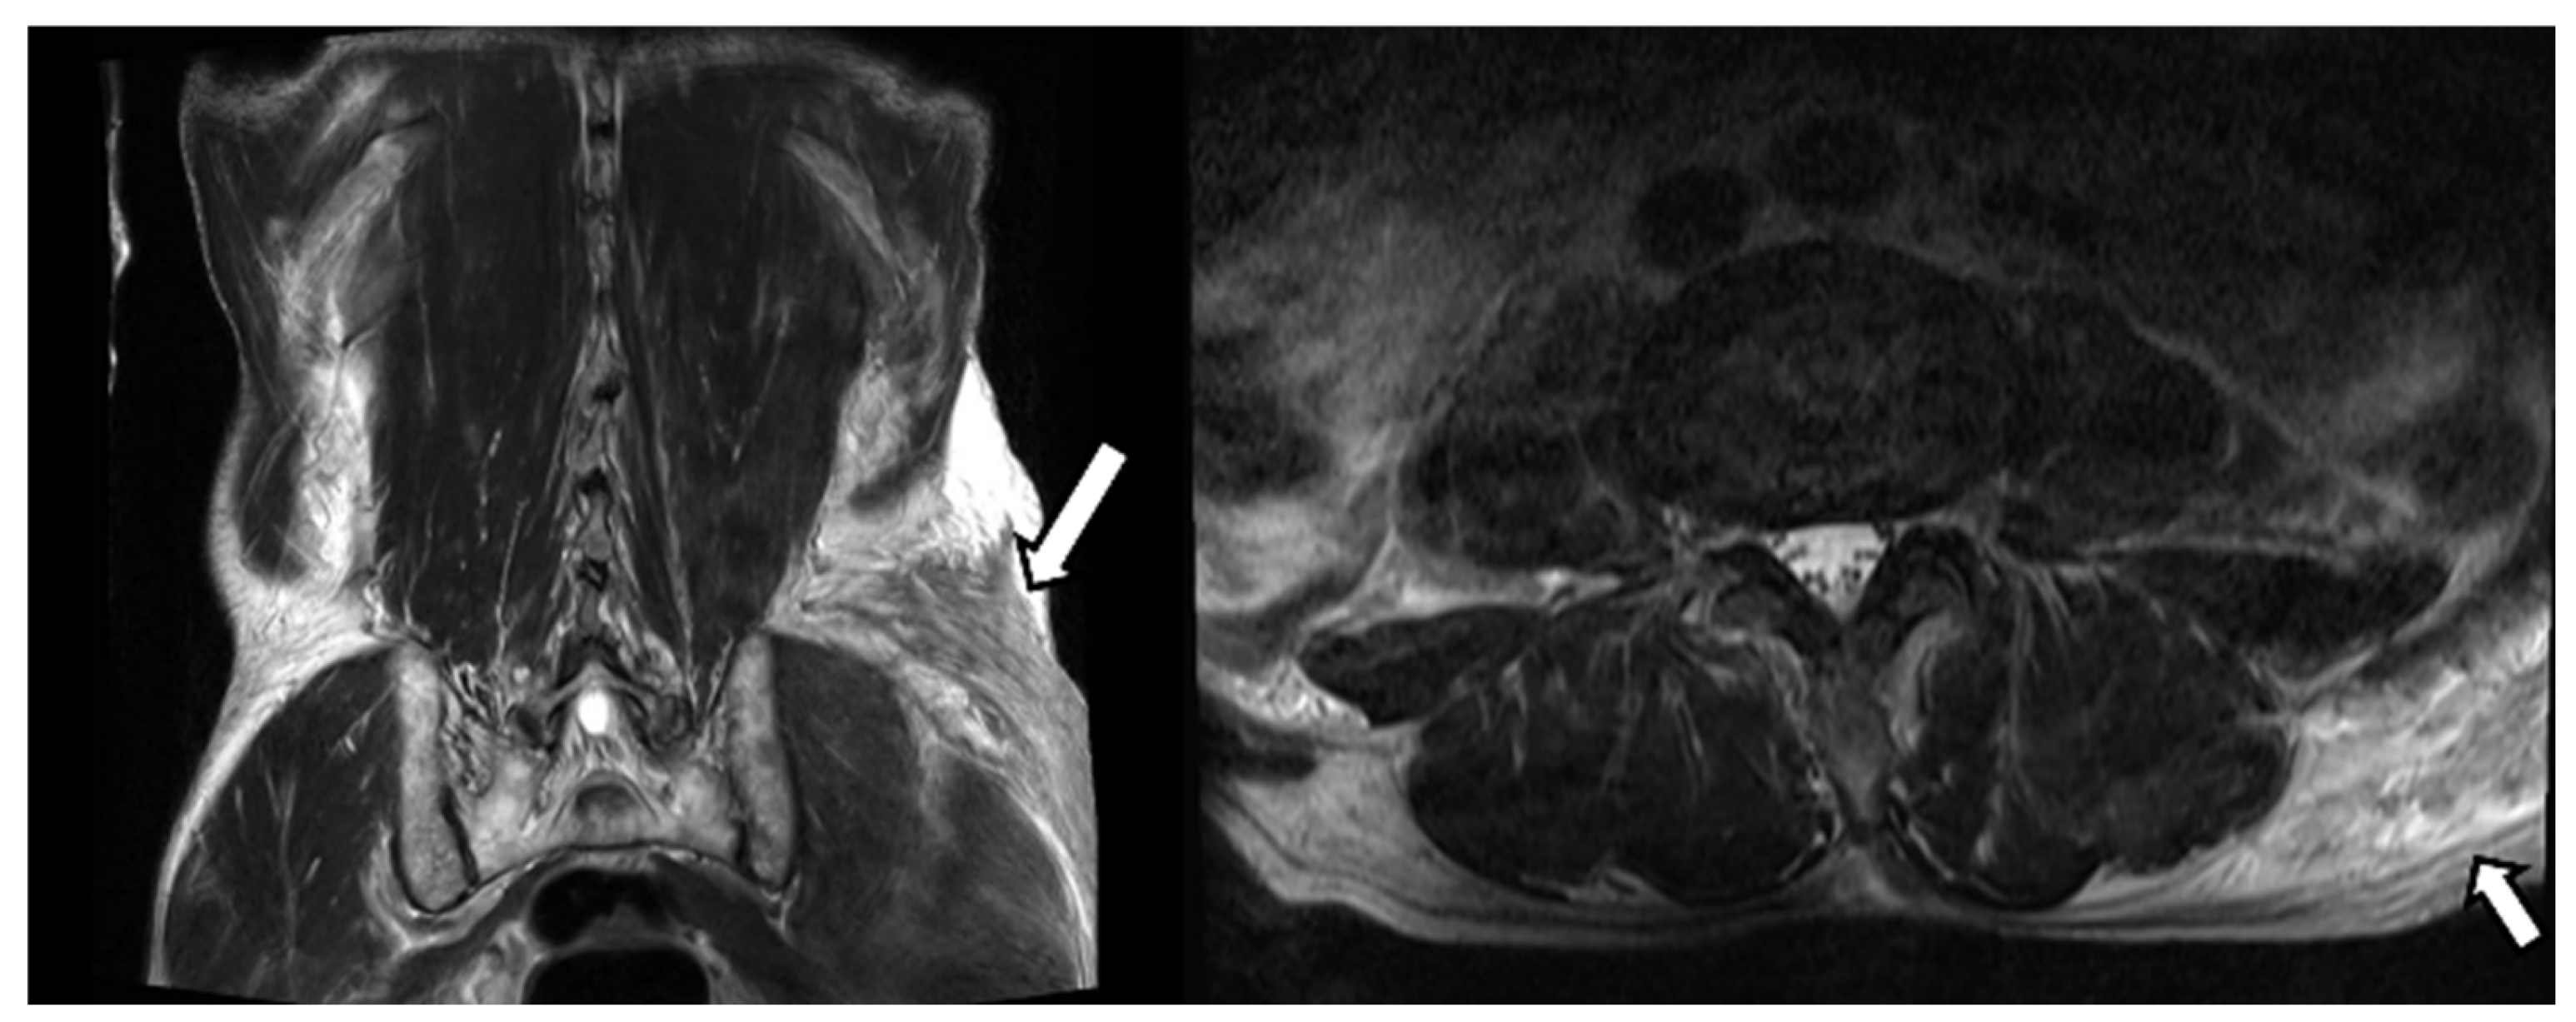

Despite conservative management, he complained of severe pain in the left hip. On the fifth day of admission, a whole-body bone scan was performed to determine if there was any other fracture. A technetium-99m methylene diphosphonate (MDP) whole-body bone scan showed an increased uptake noted in the left buttock and left flank and no other site of fracture (Figure 3). The area where the radioactivity was increased matched the location and shape of the lesion where the signal change was seen on the MRI. Furthermore, upon physical examination, we can see a considerable ecchymosis involving the left lateral chest region extending to the left buttock (Figure 4). Mild tracer uptake was also noted in the left facet joint of L4/L5, which is consistent with significant degenerative arthrosis seen on recent lumbar CT images. The osteoid formation and dystrophic calcification are thought to be the mechanisms that mediated a significant number of radiopharmaceuticals in the hematoma on whole-body bone scans [1]. The pathogenesis of the uptake of bone scanning agents in soft tissue is multi-factorial. One of the primary underlying factors is excess calcium in the soft tissue. Mechanisms leading to increased extraosseous 99mTc-MDP uptake include excess calcium in the soft tissue, extracellular fluid expansion, enhanced regional vascularity and permeability, and elevated tissue calcium concentration [2]. In this case report, 99mTc-MDP uptake in gluteal hematoma is thought to be due to excess calcium and enhanced permeability in the soft tissue. Although there is no visible calcification, the accumulation of bone tracer is possible even by microcalcification. Finally, a hematoma was confirmed based on several imaging modalities. Our patient was managed conservatively with analgesic and stopping anticoagulants. The hematoma in the soft tissue of the gluteal region is a rare occurrence and is usually seen in patients taking an oral anticoagulant, having obesity, and facing falls. Contrasted with MRI or CT findings, we could not find any fracture on the bone scan. This false-negative finding for fracture is considered attributable to the fact that for older adults, the result of bone scans may appear normal even ten days after the fracture [3]. It is well established that SPECT (single-photon emission computed tomography) or SPECT/CT (SPECT/computed tomography) has better accuracy than planar scintigraphy. SPECT/CT especially reduces the rate of equivocal lesions compared to planar bone scan due to better anatomic localization of lesions and higher lesion-to-background contrast, with increased diagnostic accuracy over SPECT alone or planar scintigraphy alone [4]. These can contribute to identifying early fractures. If SPECT or SPECT/CT had been performed on this patient, early fracture findings showing only a very slight increase in tracer uptake might have been discovered. Unfortunately, we did not have the equipment in our institution, so SPECT/CT could not be performed on the patient.

Figure 3. Technetium-99m methylene diphosphonate (MDP) whole-body bone scan shows a curvilinear-shaped hyperactive lesion in the left buttock and left flank and no other fracture site.